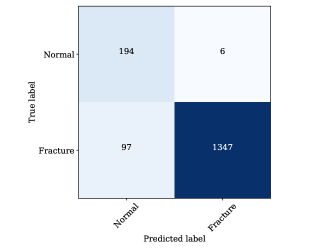

For fracture detection based on the results, it is clear that the performance of YOLOv8 outperforms YOLOv5. This is a significant improvement, especially considering that YOLOv8 is also faster than YOLOv5. Furthermore, although YOLOv8m has more parameters the mAP50 for YOLOV8s is a bit higher. On the other hand, YOLOv8m has higher mAP50-95. It is evident that YOLOv8s has demonstrated a strong ability to correctly classify images as “Normal" with 194 true positives and only 6 false negatives as presented in Figure 9.

However, it tends to make more errors when classifying images as “Fracture," as indicated by 97 false positives and 1347 true positives. This can be attributed to the nature of medical image analysis, where the cost of missing a “Fracture" (false negatives) may be considerably higher than misclassifying a “Normal" image as a “Fracture" (false positives). YOLOv8m, on the other hand, demonstrates a similar trend but with slightly improved performance when compared to YOLOv8s. It correctly classifies 192 “Normal" images and 1353 “Fracture" images. However, it still makes some errors, with 8 false negatives for “Normal" and 91 false positives for “Fracture". This model appears to strike a better balance between precision and recall for both classes, indicating a more robust classification performance.